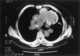

Calcified pulmonary metastasis

A lung nodule or pulmonary nodule is a relatively small focal density in the lung. A solitary pulmonary nodule (SPN) or coin lesion, is a mass in the lung smaller than 3 centimeters in diameter. [Source: Wikipedia ]